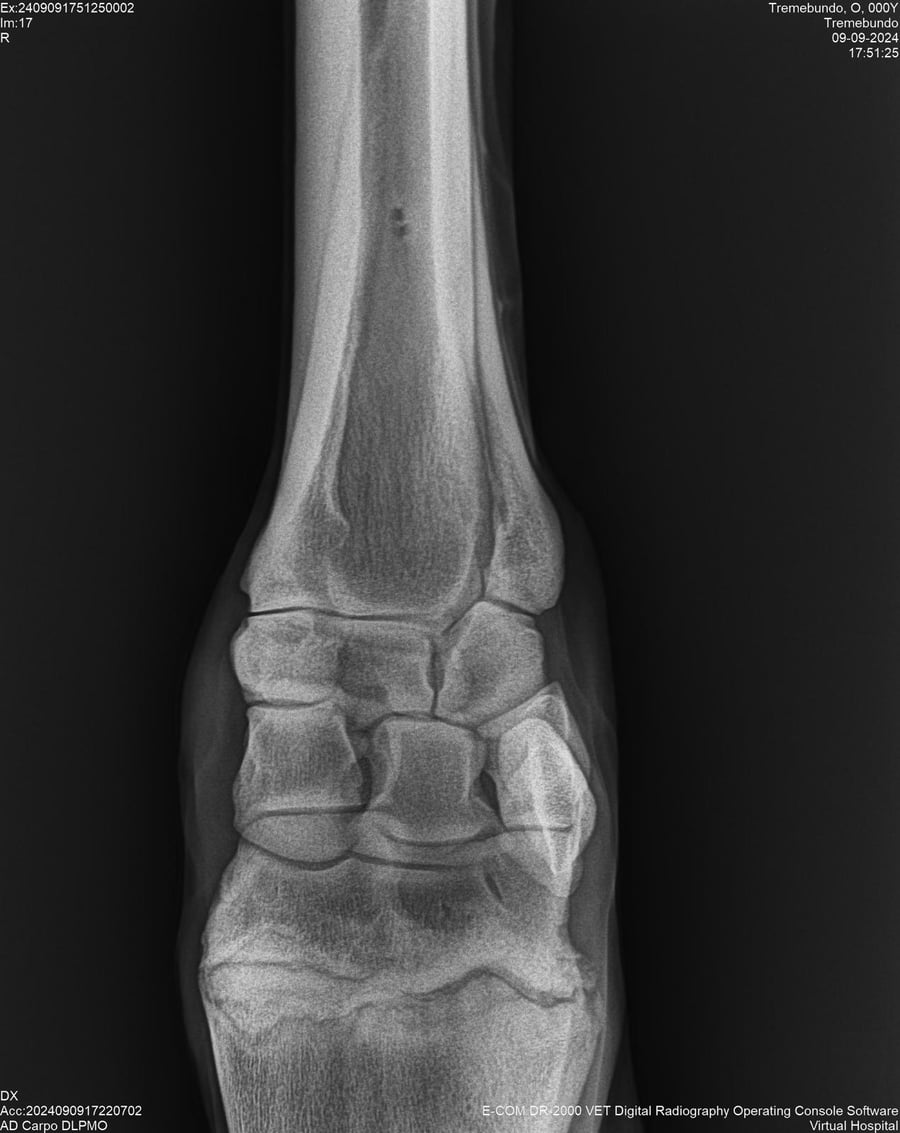

LOTE 37, TREMEBUNDO

Identificador: #291140-

Generacion 2022